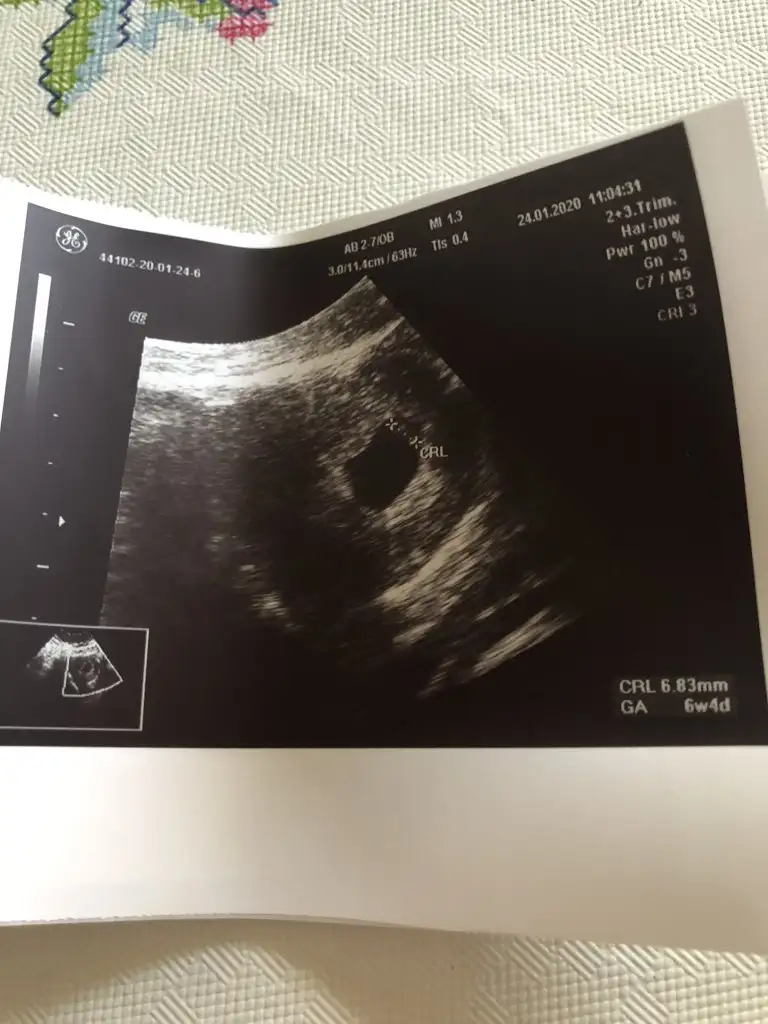

Şimdi geldim hastaneden bebişim sağlıklı sorun yok dedi ilk baştan beri 1 hafta geriden geliyoruz geç döllenme dedi kan tahlili yaptı idrar yolu enfeksiyon yok dedi ama yine de bi kültür yapalım dedi trombositlerin güzel iğneye devam edeceğiz dedi folik asit yarım yarım iç dedi bu ara folik asitle ilgili hiç hoş şeyler duymuyorum dedi sonrada folbiol değil de GEBYFOLL başlayalım dedi bizden bu kadar

Çok teşekkür ederim evet işaretli olan yer geçen hafta görmüştük canım kalp atışını zaten bu haftada izledik Zararlı olabileceğini düşünüyor doktorum o yüzden dinletmiyor q

Çok teşekkür ederim evet işaretli olan yer geçen hafta görmüştük canım kalp atışını zaten bu haftada izledik ☺ Zararlı olabileceğini düşünüyor doktorum o yüzden dinletmiyor q